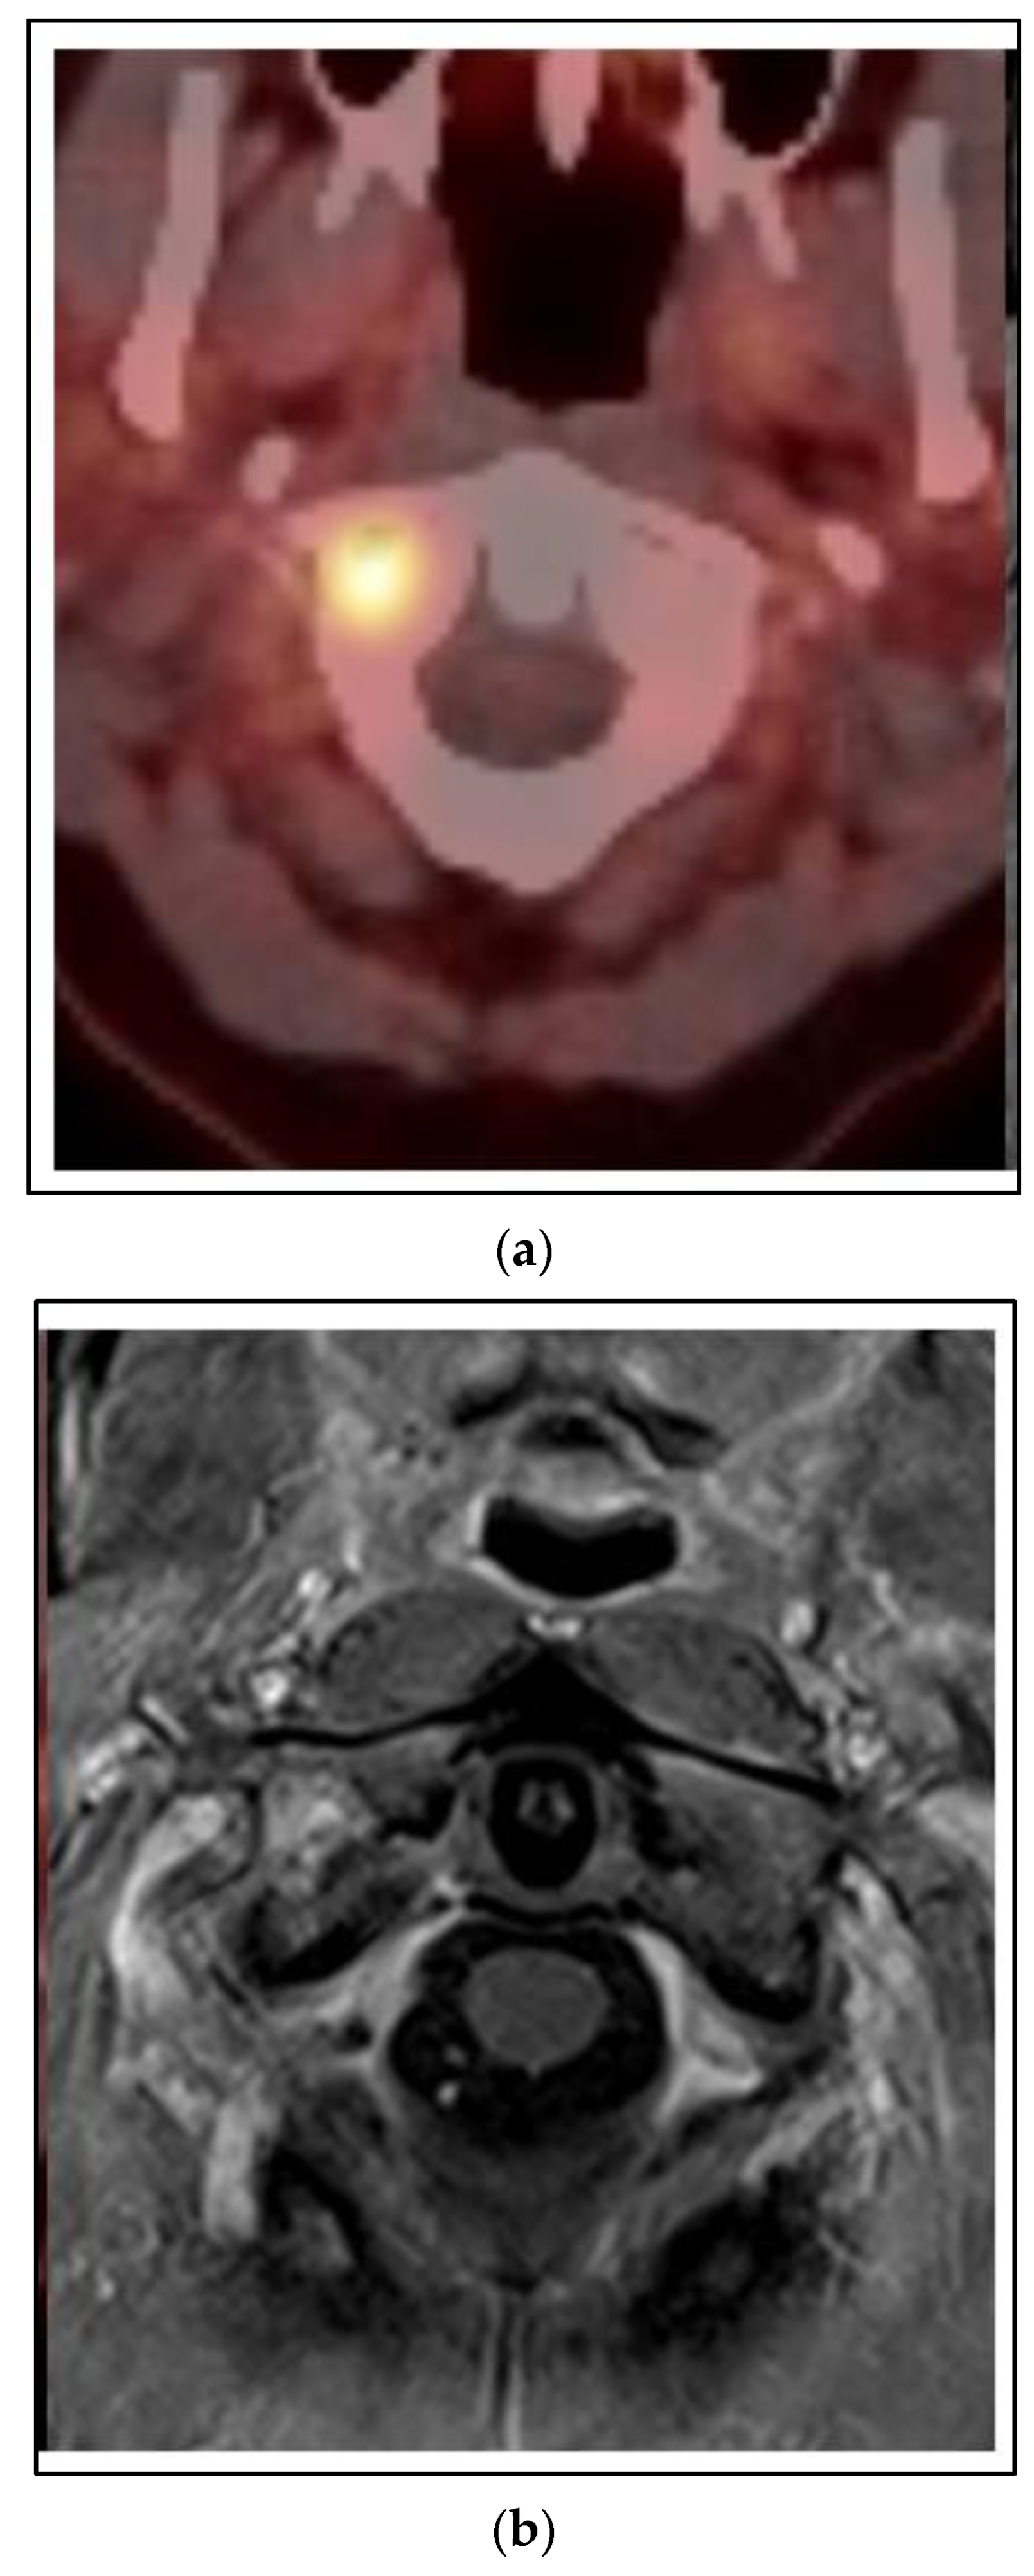

In the previous case, there was not a complete response to neoadjuvant chemotherapy in the local-regional disease or in the sternum. However, what is the role of SBRT if an oligometastasis is more responsive to systemic therapy? Figure 3 shows images of a CT scan of the chest conducted for the staging of breast cancer showing three suspicious lung nodules at diagnosis that were PET-avid. The woman is a 68-year-old who presented with right breast cancer T3 N1 M1, with no other signs of metastatic disease. She had neoadjuvant chemotherapy with TCHP. She had a clinical complete local-regional response. She then had lumpectomy and sentinel node biopsy, followed by local-regional radiation. Her first three month restaging CT showed a partial response in the lung nodules, and by the six month CT scan on HP alone, there was a complete resolution of the lung nodules. She continues on HP over three years from initial treatment and is without signs of recurrence or progressive disease.

Figure 3. Case 2: Simultaneous oligometastases. Three representative axial images from a CT scan obtained for initial staging of breast cancer showed 3 highly suspicious lung nodules each marked with a red arrow that were PET-avid. With systemic therapy alone there has been a complete response in the lung nodules for greater than 3 years.